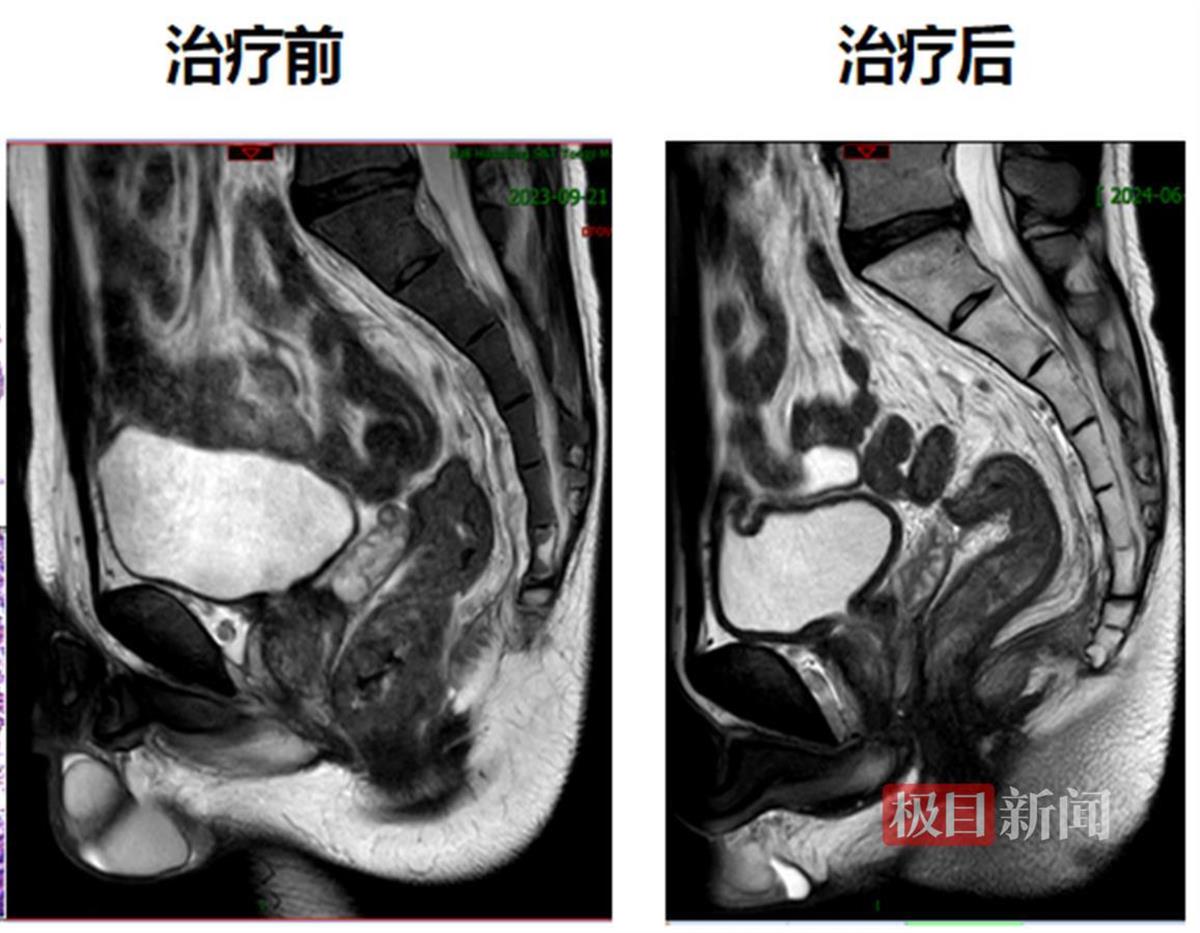

今年33岁的小江(化名)是接受该创新治疗模式的患者之一。2023年9月,他因便血1年多,最近一个多月又出现肛门坠胀在外院就诊,腹部CT检查提示直肠下段肿瘤性病变,经活检证实为腺癌。医院建议进行手术治疗,但小江保肛意愿强烈,为寻求进一步治疗,于是来到协和医院就诊。入院后,经过磁共振检查及病理会诊,他被确诊为低位直肠腺癌T3N2M0,肿瘤下缘距离肛门口仅2厘米,保肛难度非常大。

经过胃肠外科、腹部肿瘤科、影像科、病理科等多学科讨论后,最终决定采用新疗法。2023年9月,小江接受了5次直肠病灶及淋巴结引流区放疗,随后进行化疗联合免疫新辅助治疗,今年1月再次复查肠镜发现,他的直肠下段肿瘤病灶已经消失,获得了临床完全缓解。这也意味着小江的肿瘤术前完全消退,后续接受规范的监测和复查即可。